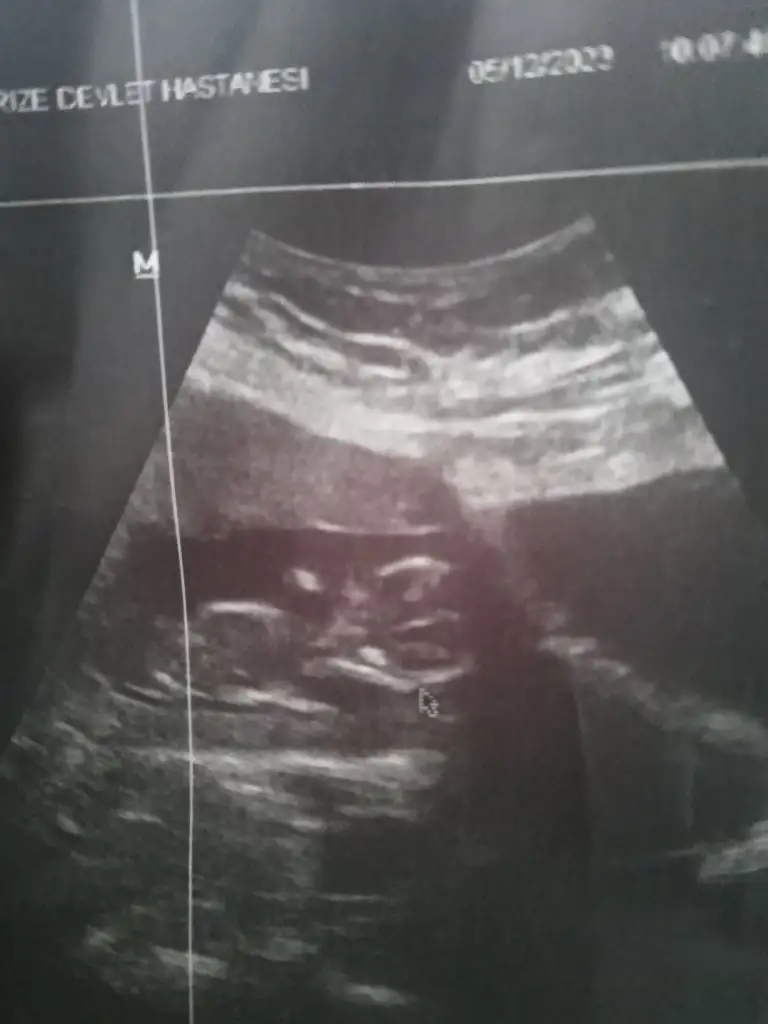

İçime kız gibi doğduSızce ne cınsıyetı arkadaslar

Ben de bakınca erkek gibi hissettim niyeyseSızce ne cınsıyetı arkadaslar